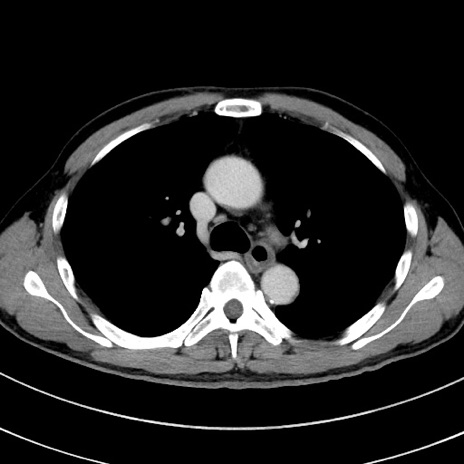

症例8(横断像)

【症例】 60歳代男性

【主訴】 黒色吐物

【現病歴】 4日前から嘔気自覚、2日前の朝食後にも嘔気あり、自分で手で嘔吐反射起こし嘔吐したところ血が混ざっていたため受診。

【既往歴】 5年前汎発性腹膜炎を伴う急性虫垂炎で手術、高血圧、前立腺肥大症、高脂血症

【身体所見】 腹部正中に手術癩痕あり 腹部平坦・軟圧痛なし膨満感あり

【データ】WBC 8400、CRP 4.54